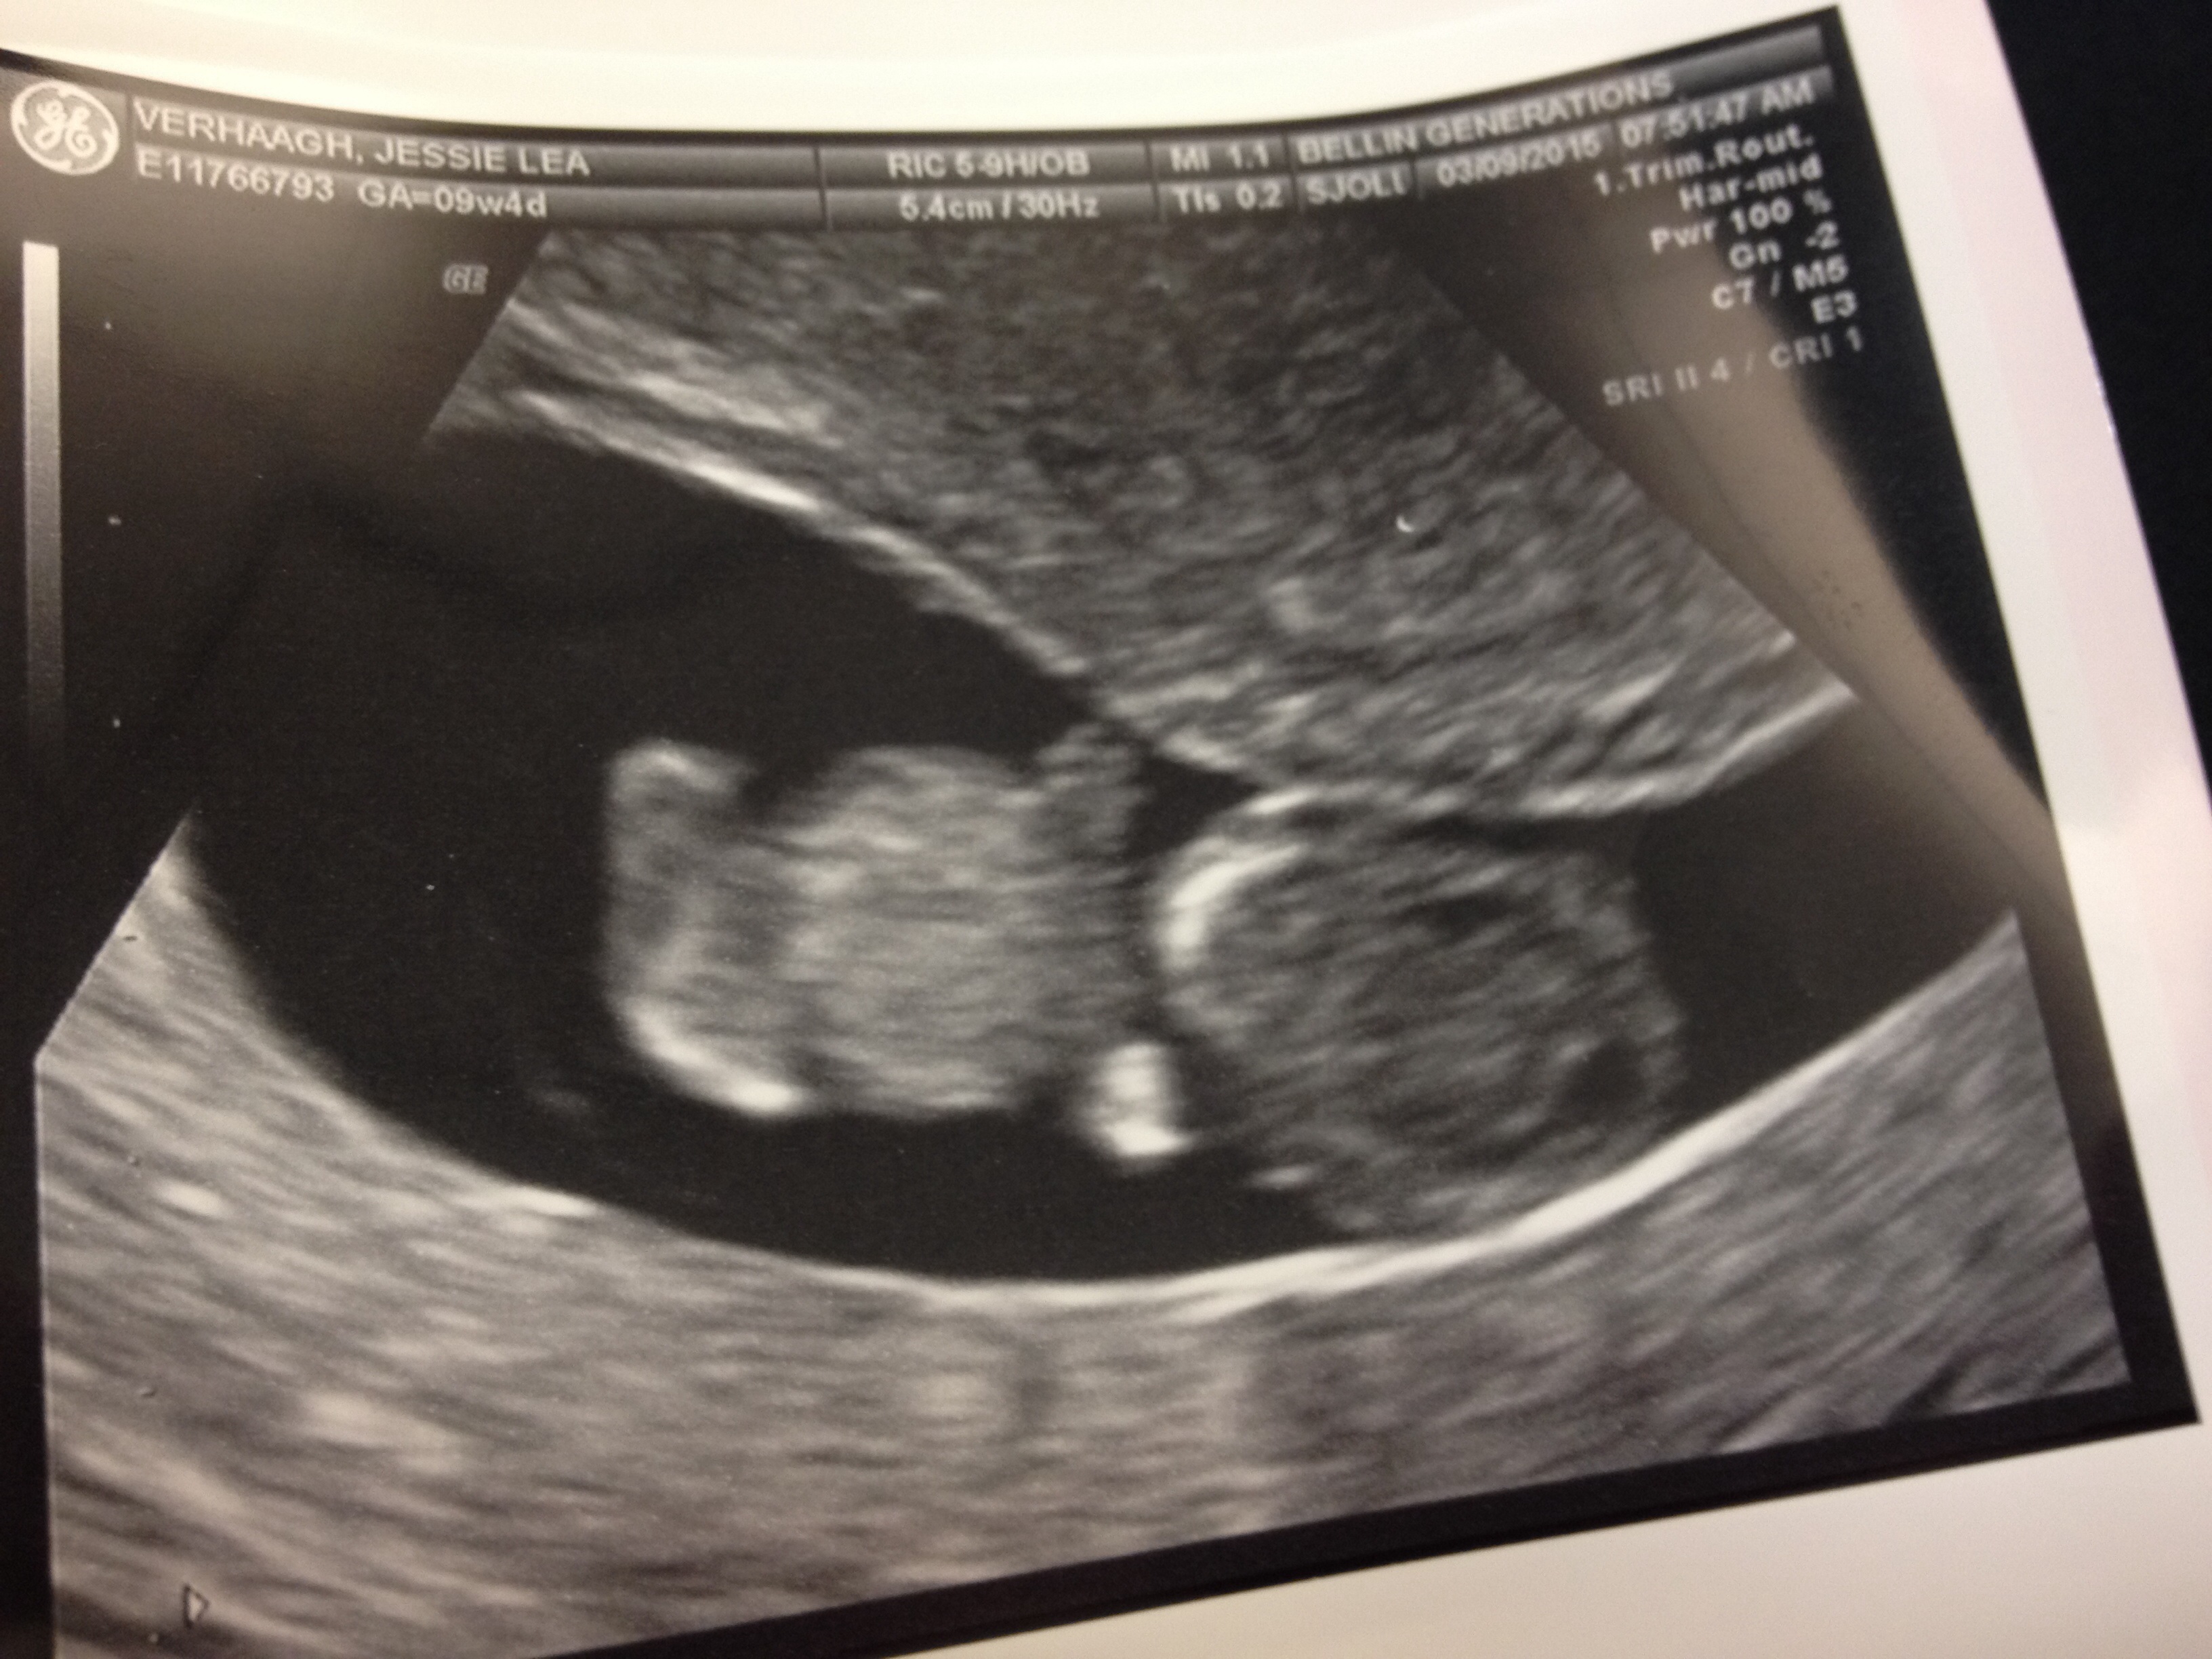

Just had our dating scan today! 8 weeks exactly! Here is cub's head & little arm/leg stumps! I have a cyst in an ovary but was told that should go away. This is our first!